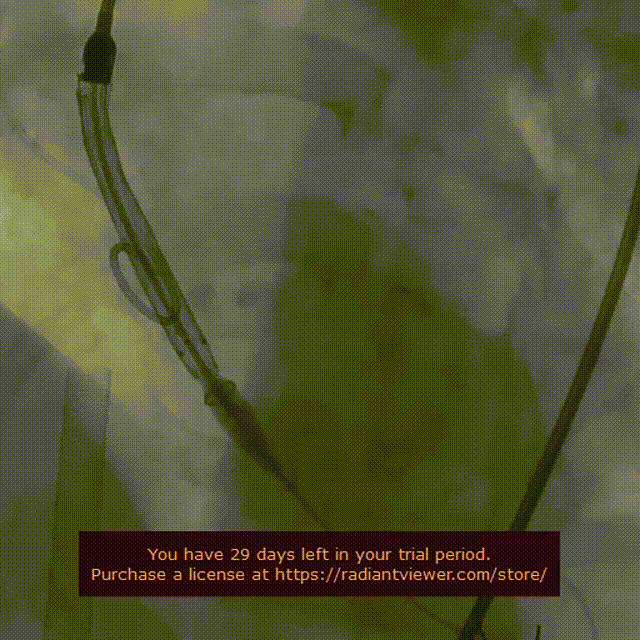

瓣膜释放完毕后心脏停跳

情况稳定后造影图

患者主动脉根部结构复杂,极重度钙化,腹主动脉及双侧髂总动脉存在环形钙化。常规股动脉直径入路困难,吴延庆教授组织团队在术前制定完成手术预案,根据病人情况选择采用All IN ONE技术通过右侧股动脉途径入路进行手术。术中未使用起搏器,通过超硬导丝诱发室颤来降低血压心率的方法,配合调整ECMO转速来完成球囊预扩与VenusA L26瓣膜释放置换。释放完毕后出现心室颤动,予以电除颤后,心脏停搏,胸外按压三十秒恢复自主心率,造影观察后有少量反流,测得压差9mmhg,手术效果完美,瓣膜置入位置良好、形态完整。